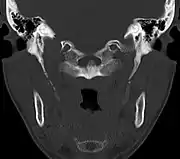

|

El diagnóstico se realiza en base a los signos y síntomas descritos y debe ser confirmado mediante pruebas de imagen. Los síntomas suelen empeorar en la palpación de la apófisis estiloides.[10]

La apófisis alargada o calcificación del ligamento estilohioideo suelen mostrarse fácilmente a través de una prueba radiográfica. De forma adicional se puede realizar un TAC para confirmar el diagnóstico y ver qué estructuras están siendo afectadas.[10]